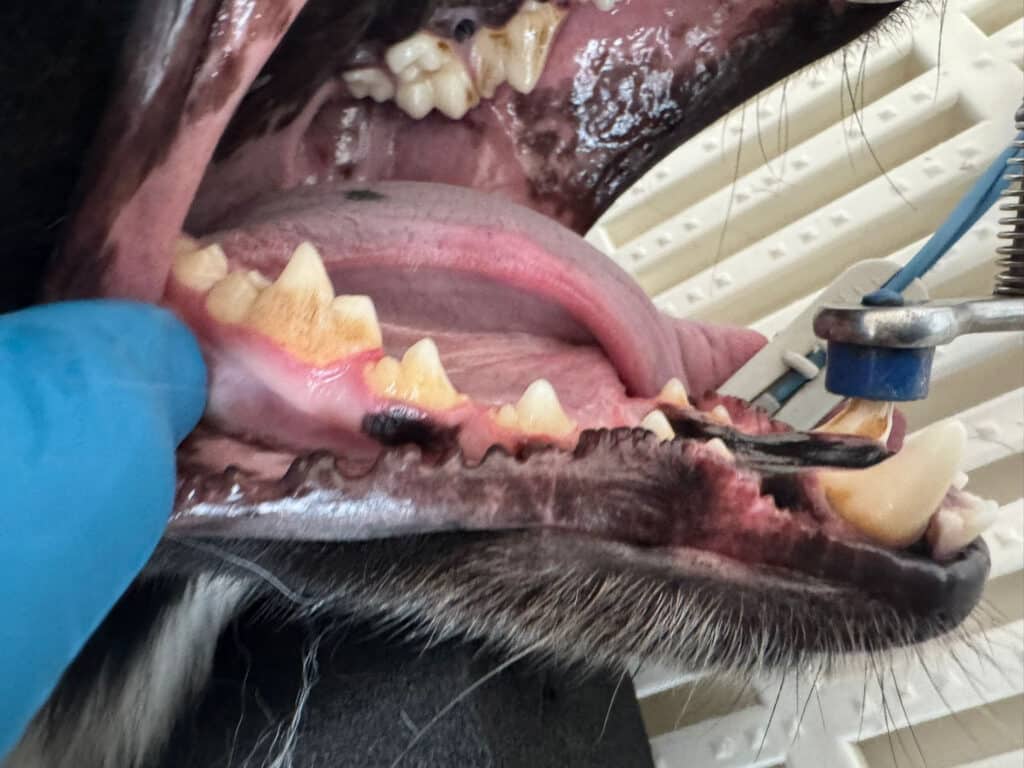

Beispielbilder vorher - nachher

Vorher

Beispielfotos unserer Patienten

Das sollten Sie behandeln lassen!